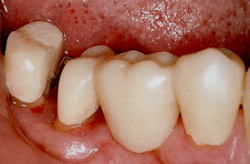

実際に抜歯になった上顎大臼歯です。 |